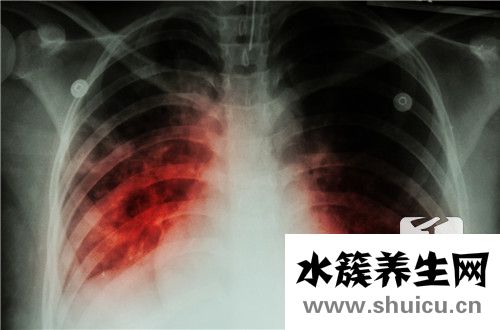

大家都知道人体内有很多炎症性疾病,但大多数人并不清楚炎症临床表现的全过程。比较常见的炎症是由感染因素引起的,比如肺炎、肾炎、肝脏炎症,大家都比较熟悉。当这种人体器官发炎时,身体会开始自己的防御过程,然后出现一系列的临床表现,整个过程会有详细的改变。

发炎的基本临床表现一般 归纳为部分组织的霉变、外渗和增生。

一般说来,炎症反应或发炎的初期,通常渗出性和霉变占位性病变较明显,而炎症或发炎的中后期,则增生占位性病变较突显。

发炎的基本临床表现是霉变、外渗和增生。组织和体细胞的转性、坏死统称霉变,仅是基本临床表现的一部分內容;而红、肿、热、痛和功能问题则意味着着发炎的外界主要表现;发炎组织的炎症性血肿和水肿只包括了发炎的一部分血管转变和液體外渗,不可以包含发炎的基本临床表现;而周边血白细胞多和发炎地区白细胞计数侵润则意味着了一部分发炎的全身反映和部分炎体细胞侵润,都不全方位。